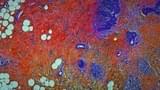

医師の視点から外科手術を見つめ、人体の神秘と人間の恐怖の根源に迫ったドキュメンタリー。

パリ北部近郊の5つの病院のオペ室を舞台に、普段は決して見ることのできない手術時の医師視点のカメラや内視鏡カメラなどの映像を使用しながら、脳や大腸、眼球、男性器などさまざまな外科手術や帝王切開の模様を映しだす。さらに、死と隣りあわせの職場で働く医療従事者たちの心境や、死体安置所での「おくりびと」たちの仕事ぶりをとらえ、医療とは何か、そして肉体と魂とは何かという疑問を探る。